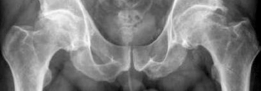

Image

The Dunn lateral radiograph confirmed the presence of a prominent cam deformity, with an alpha angle measured at 72 degrees, significantly above the normal threshold of 50-55 degrees. This confirmed the clinical suspicion of cam-type femoroacetabular impingement as the primary etiological factor for the degenerative changes. The lateral center-edge angle was measured at 34 degrees, indicating adequate acetabular coverage without frank dysplasia or significant protrusio acetabuli.